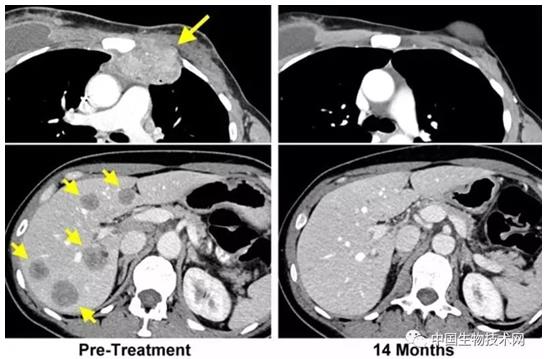

当时49岁的Perkins首先是接受了化疗来阻止右侧乳房中的肿瘤继续生长,但是以失败告终。之后她被选择接受这种新型疗法。期间,肿瘤还扩散到了她的肝脏和其他部位,这也是医生们决定对她进行免疫治疗的决定因素之一。幸运的是,治疗结果非常成功:她体内的癌细胞被完全清除了,即使两年后,医生们也没有在她体内发现癌细胞的踪迹。这是该方法首次取得成功。根据NCI外科主任Steven Rosenberg的说法,研究人员在过去曾经利用该技术使六位罹患结肠癌或宫颈癌患者难以治疗的肿瘤缩小了。